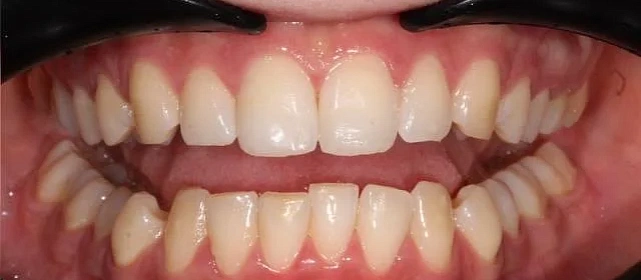

Неровные зубы.

Обе челюсти сужены — зубам не хватало места, они стояли скученно на верхней и нижней челюсти. Нарушена кривая смыкания — жевательные зубы были на разной высоте.

Проблема: Пациентка живёт за рубежом и обратилась с жалобами на неровные зубы. При осмотре обнаружили сужение обеих челюстей, скученность на верхней и нижней, а также деформацию кривой смыкания — жевательные зубы стояли на разной высоте, из-за чего нагрузка при еде распределялась неравномерно. Дополнительная сложность — пациентка не могла приезжать на визиты часто.